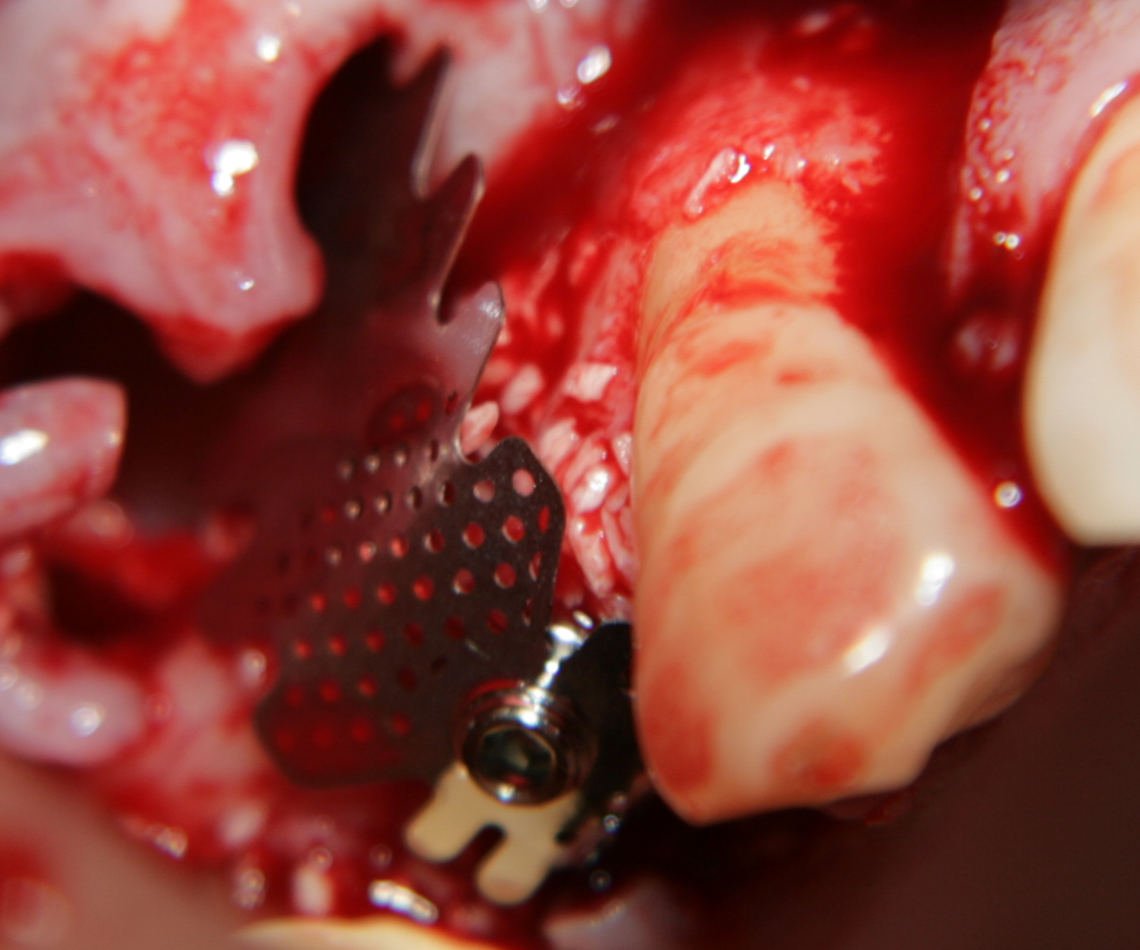

Титановите мембрани са твърди, ригидни приспособления, които се поставят в участъци с необходимост от увеличаване на костния обем - най-вече в областта на имплантологията, но също при радикуларни кисти и много рядко след екстракция на ретинирани мъдреци, при дефкетни фрактури, пострезекционни дефекти на челюстите, тежки остеомиелити и специфични възпаления на костта. Идеята на титановата мембрана е да предпази меките тъкани от колапс, поне за известен период от време, през който период под мембраната да започне костообразуване. През първите шест - осем месеца титановата мембрана оказва своя ефект, след което вече е безсмислено да остава в устата на пациента.

При операции с цел изграждане на допълнителн костна тъкан (костна пластика) винаги е добре да се перфорира кортикалната пластинка на костта. През тези перфорации излизат костни клетки, които постепенно прорастват в котозаместващия материал и синтезират нова костна тъкан. Перфорациите могат да се извършат с кръгло борче или с АСМ - фрезата на Neobiotech - Южна Корея.

Tent screw - винтове за

фиксиране на титановата мрежа

Около винтовете се поставя костозаместител, добре е да се размеси с

автогенна кост

Титанова мембрана

PRF